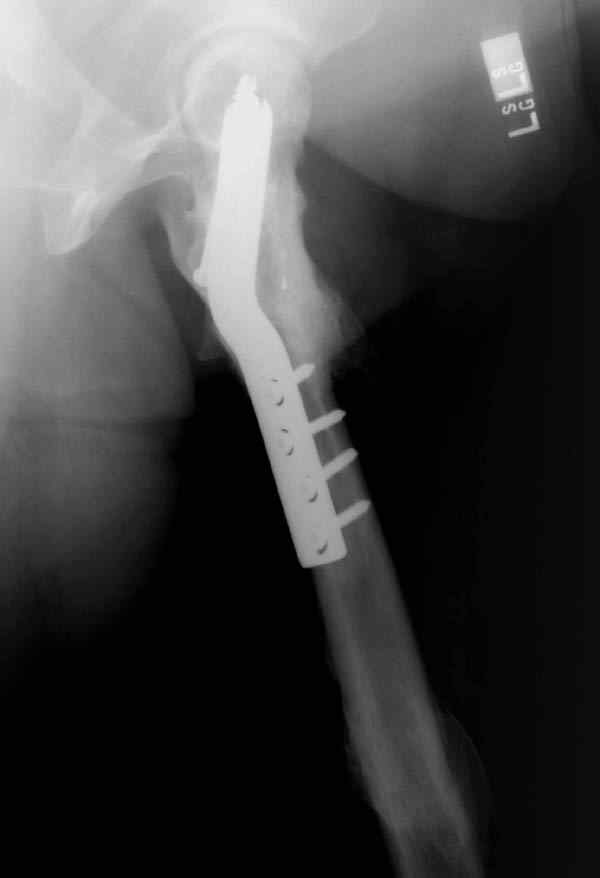

Вложение не в текстовом формате было извлечено…

Имя     : ipsilateral neck shaft postop.JPG

Тип     : image/jpeg

Размер  : 36845 байтов

Несмотря на пессимистические прогнозы, у молодых

коррегирующая вальгусная остеотомия является более

приемлемым.

Представленные случаи доказательства тому, что еще

имеется резервы на восстановление даже у 5-6 месячных ложных суставов шейки.